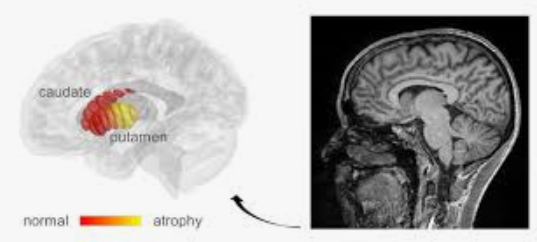

파킨슨병은 운동 조절에 관여하는 뇌의 일부인 흑색질에서 도파민 생성 세포의 점진적인 퇴화로 인해 발생하는 운동 장애 증상입니다. 유전적 요인과 환경적 요인이 복합적으로 작용하는 것으로 널리 알려져 있지만 이 퇴행의 원인은 거의 알려지지 않았습니다.